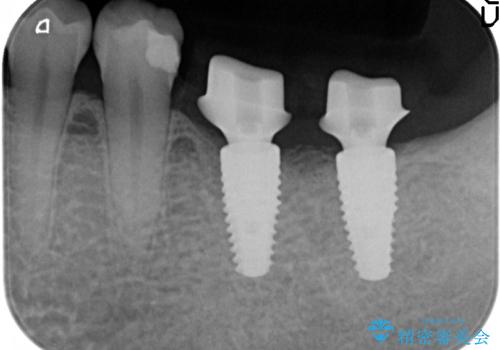

左下にインプラント(ストローマン)を2本埋入し、オールセラミッククラウンによる補綴を行いました。

- オールセラミッククラウン…¥100,000×2、仮歯…¥10,000×2、インプラント(ストローマン)…¥200,000×2、カスタムアバット…¥100,000×2費用は治療当時の料金となります

当院では主にストローマンという種類のインプラントを治療に用いています。

ストローマンは世界的にもNo1のシェアを誇り、骨との適合にも優れたインプラントです。

カスタムアバットメントについて

カスタムアバットメントは患者様それぞれの歯茎に合わせて製作されたオーダーメイドのアバットメントです。

既製のアバットメントに比べ適合がよく、高い清掃性を誇ります。